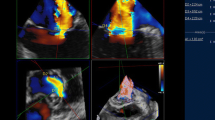

In 2021, a 67-year-old Caucasian woman presented to our outpatient cardiology clinic with worsening exertional breathlessness with no physical stigmata of heart failure. Transthoracic echocardiography (TTE) demonstrated an aortic regurgitation (AR) with a pressure half-time of 597 ms, a vena contracta of 0.45, but visual assessment was graded as moderate to severe AR (Fig. 1a, b, Additional file 1: Video S1). A cardiovascular magnetic resonance (CMR) with four-dimensional flow (4D flow) was done to better quantify the AR and the left ventricular (LV) volumes. CMR was performed on a 3-T Discovery 750w GE system (GE Healthcare, Milwaukee, WI, USA) equipped with an eight-channel cardiac coil. CMR cine images in two-, three-, and four-chamber views were obtained during end-expiratory breath-hold with a balanced steady-state free precession (bSSFP), single-slice breath-hold sequence. Images encompassed the entire heart, aortic valve, and ascending aorta using the following scan parameters: HyperKat acceleration with a factor of 2, field of view 340 mm × 340 mm, acquired voxel size 3 × 3 × 3 mm3, reconstructed voxel size 1.5 × 1.5 × 1.5 mm3, echo time (TE) 3.5 ms, repetition time (TR) 10 ms, flip angle 10°, and 30 cardiac phases. Four-dimensional flow analysis of peak mitral inflow velocity was performed using CAAS MR software (prototype version 5.2; Pie Medical Imaging, Maastricht, the Netherlands).

Mitral inflow assessment of peak early (E-wave) and late (A-wave) inflow velocities. a, b | Transthoracic echocardiography: turbulent aortic regurgitation demonstrated in the apical 2 chamber (a). Pulsed-wave Doppler echocardiography at the tip of the mitral valve leaflet results in very turbulent early filling which prohibited peak mitral inflow E-wave velocity assessment. c, d On 4D flow CMR assessment by peak velocity tracing within the three-dimensional space of the streamlines, the peak velocity during early filling (c) and late filling (d) were recorded by limiting the streamline assessment to length of the mitral valve leaflets. The peak velocity is depicted as the orange ball for mitral inflow and as red ball for aortic regurgitation in the three-chamber view. e, f Both transaortic and transmitral peak velocity traces are presented. Compared with pulse-wave echocardiography, a clearer depiction of peak velocity is seen for both E-wave and A-wave

The LV was not dilated (indexed LV end-diastolic volume 84 ml/m2 and end-systolic volume 26 ml/m2) and had preserved function (ejection fraction 69%). CMR elucidated the AR severity to be mild to moderate (AR fraction 22% with no holo-diastolic reversal in descending aorta). We used novel three-dimensional peak velocity tracing of the transvalvular flow streamlines to investigate whether we could map out the mitral inflow peak diastolic early (E-wave) and late (A-wave) velocities, which were challenging to assess by pulsed-wave Doppler echocardiography (Fig. 1c, d, Additional file 2: Video S2). The flow streamlines can track blood flow from the mitral annulus, and hence there is less chance of picking up the peak velocity of aortic regurgitation flow. Even though diastolic mitral flow is likely to be blunted by the AR, this method allows to at least assess peak velocity through the mitral valve leaflets (Fig. 1e, f). This case highlights that pulsed-wave Doppler echocardiography has a limited role in the assessment of mitral inflow in the presence of AR, limiting its use in LV diastolic and mitral stenosis assessment when AR is present. Secondly, we show for the first time that 4D flow CMR plays a complementary role in teasing out the peak mitral inflow velocities in patients with AR.

Additional file 1: Video S1. Video demonstrating turbulent aortic regurgitation using transthoracic echocardiography in the apical 2-chamber view. Presence of aortic regurgitation causing turbulent early-filling of mitral inflow.